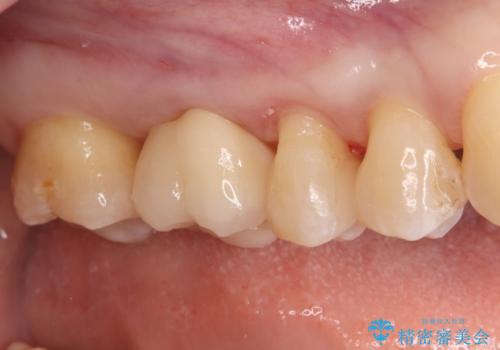

- 左上奥歯に入っている金属の詰め物(メタルインレー)の見た目を改善したいという主訴でご来院されました。お口の中の金属をなくしたいという患者様のご希望を踏まえ、天然歯に近い色と質感を持つセラミックインレーに交換する治療計画を立案。これにより、見た目の改善だけでなく、金属アレルギーのリスクを排除したメタルフリーの環境を実現することを目指しました。

治療では、まず古い金属のインレーを慎重に取り外しました。金属の下に隠れていた虫歯の再発がないかを確認し、歯を丁寧に形成。その後、精密な型取りから患者様の歯の色に合わせたオーダーメイドのセラミックインレーを作製しました。セラミックは、自然な光の透過性を持つため、周囲の歯と区別がつかないほどの美しい仕上がりとなります。適合性の高いセラミックインレーを装着することで、再発のリスクを抑えつつ、長年のコンプレックスだった銀歯がなくなり、笑顔でも気にならない自然な奥歯を取り戻していただけました。